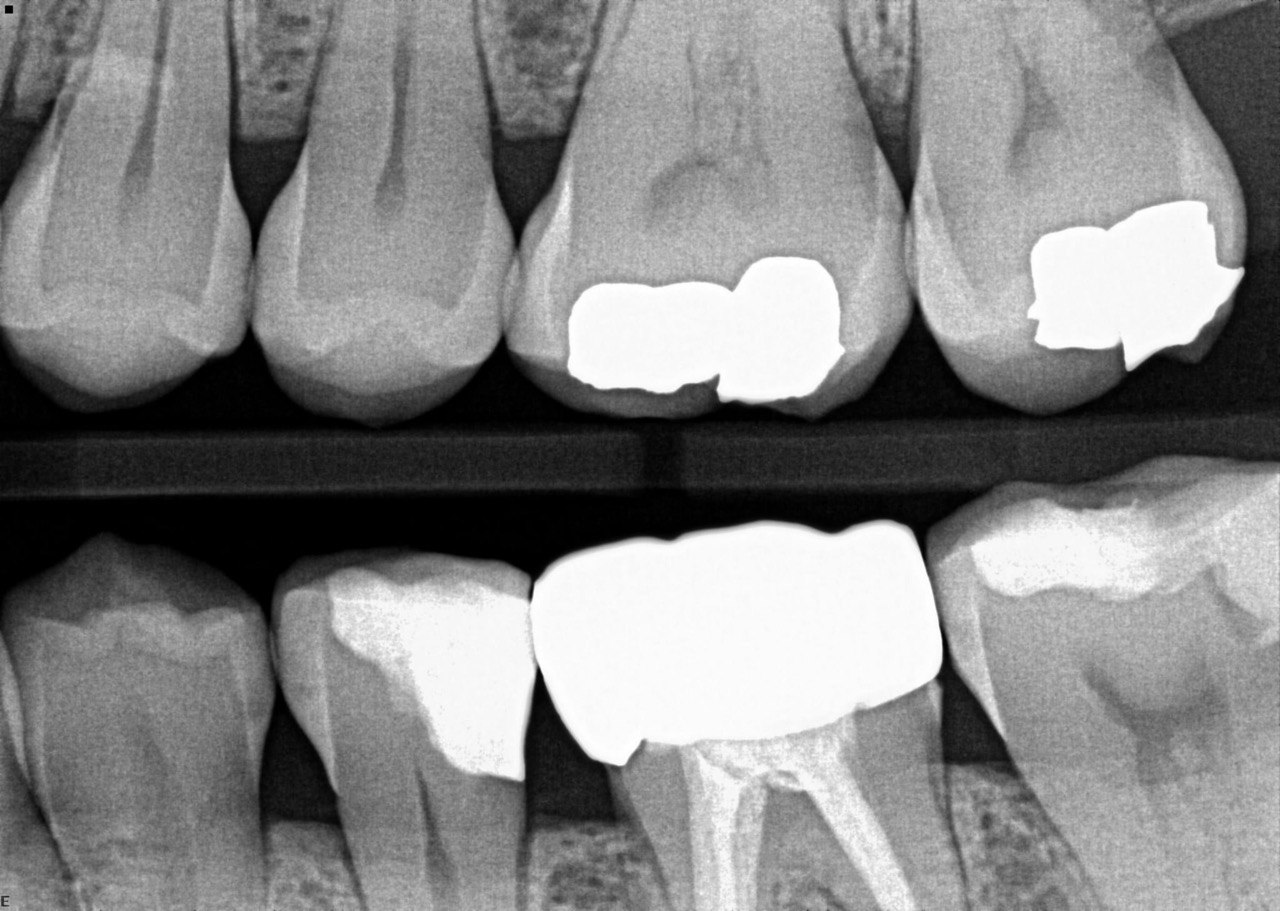

3. What surface require restoration?